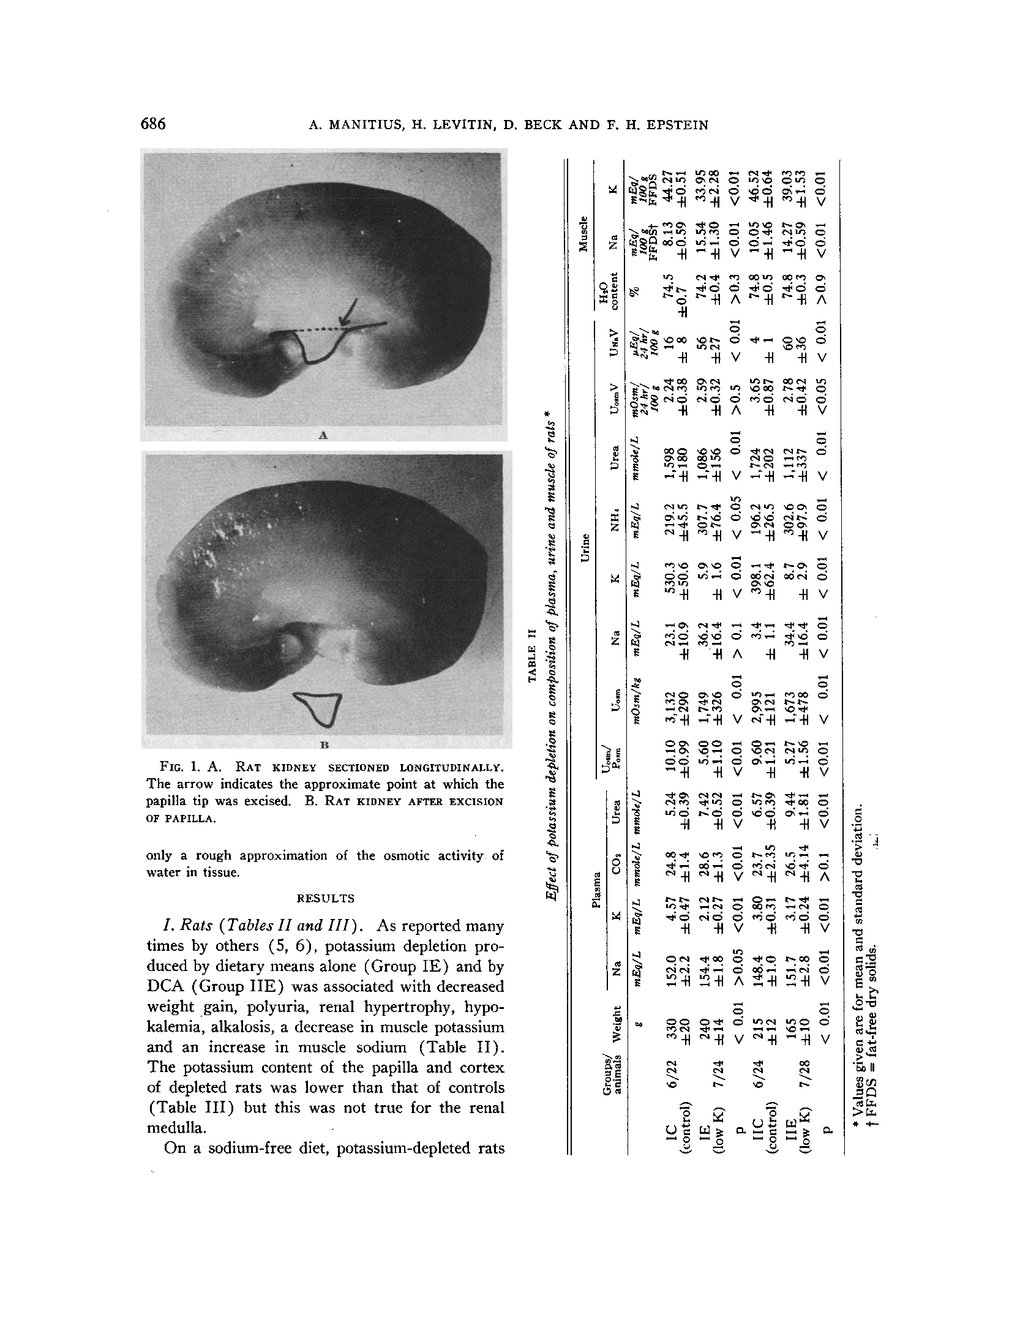

ON THE MECHANISM OF IMPAIRMENT OF RENAL CONCENTRATING ABILITY IN POTASSIUM DEFICIENCY